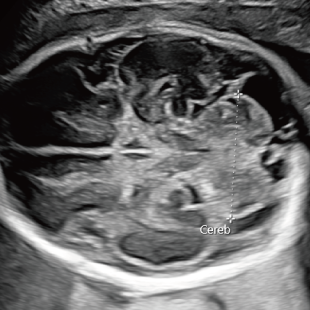

Voluson Expert 22®(GEHealthcare)という産婦人科領域におけるハイエンド超音波診断装置を使用しています。 従来機種と比べ、より高精細な画像描出性能と高度な解析機能を備えており、 胎児の発育や形態をより詳細に観察することが可能です。